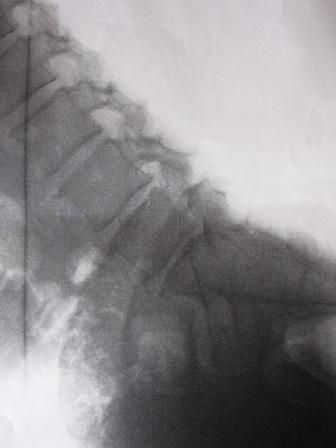

腰痛は20代の頃からの長いつき合いである。

常に腰に時限爆弾を抱えながら働いている。

先日、介護技術講習を受けた。